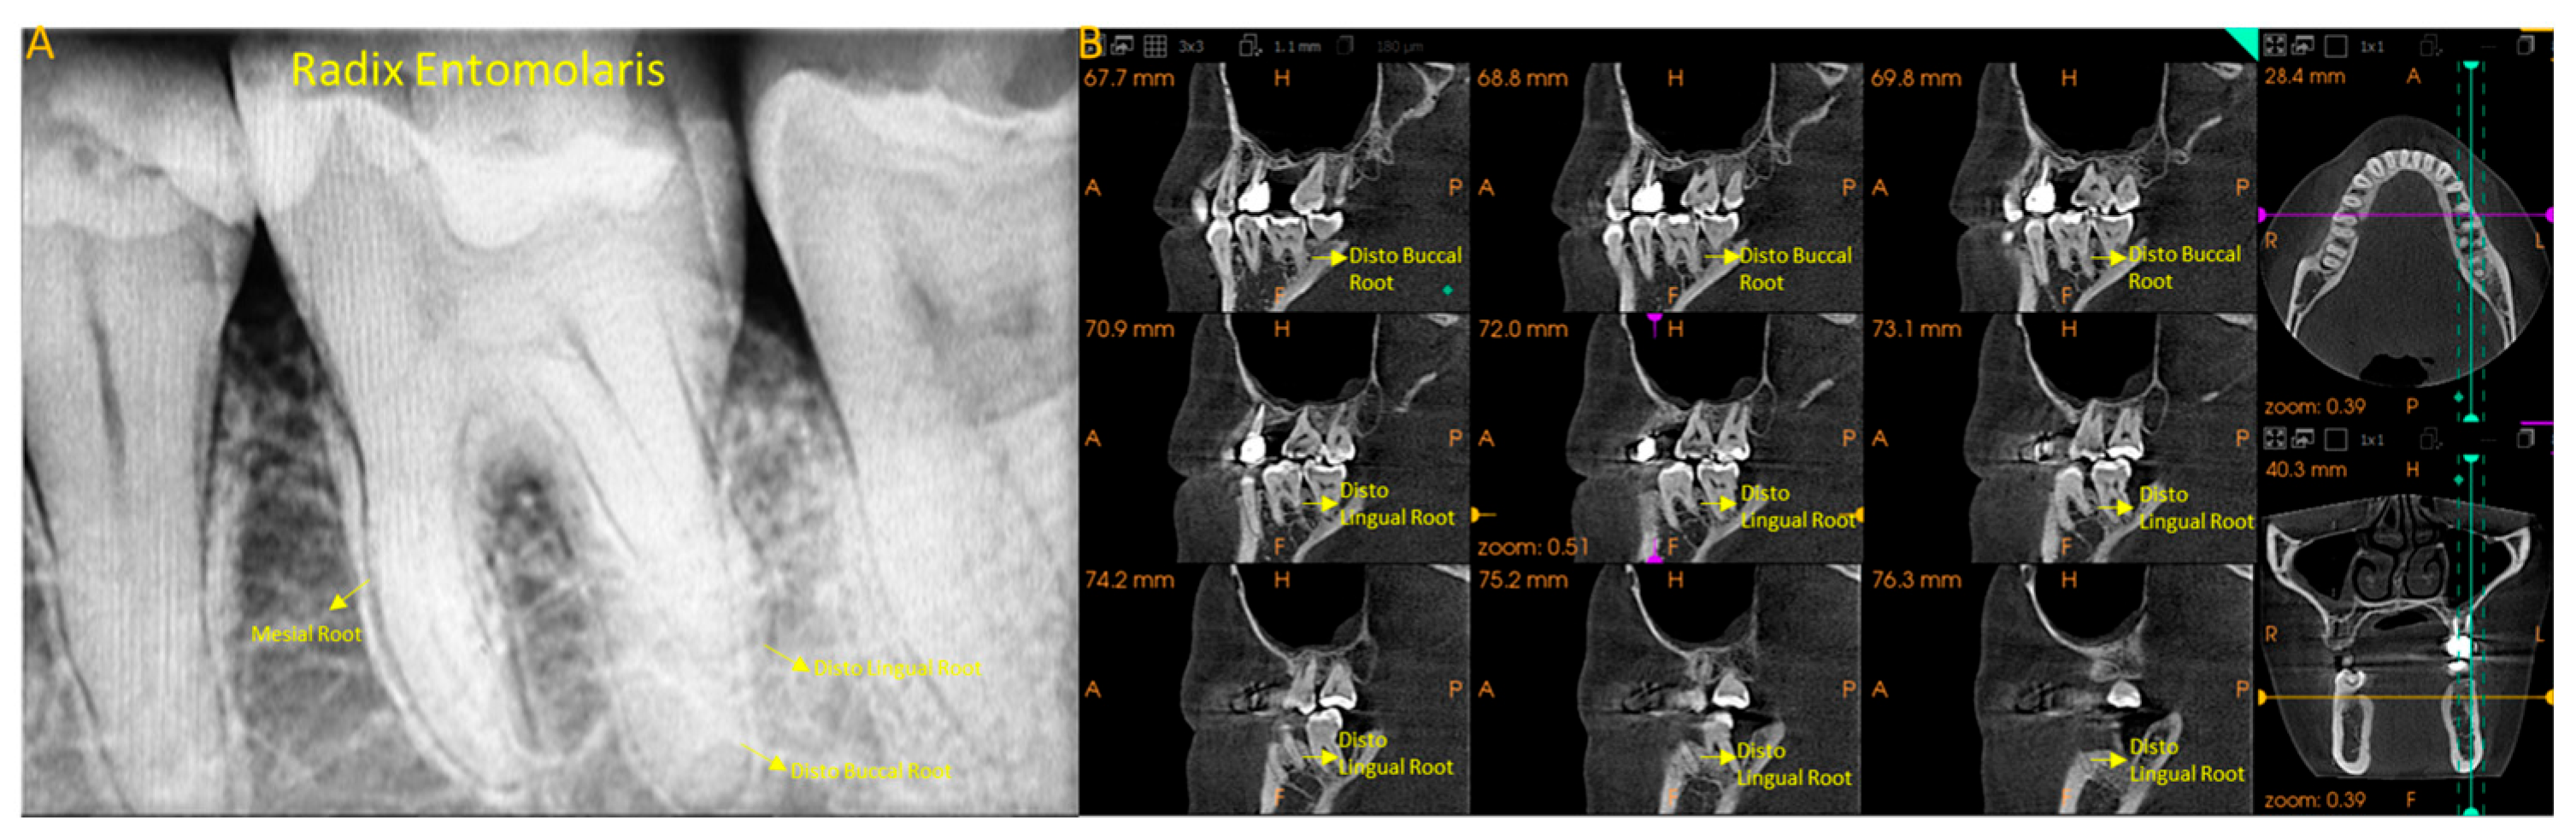

Figure 3 presents the MFM with additional DLR represented in periapical and CBCT images.

Figure 3.

Radix Entomolaris. (A), intraoral periapical radiograph of MFM showing three roots: mesial, distobuccal, and distolingual (DLR); (B), CBCT image of the same showing the presence of a separate DLR.